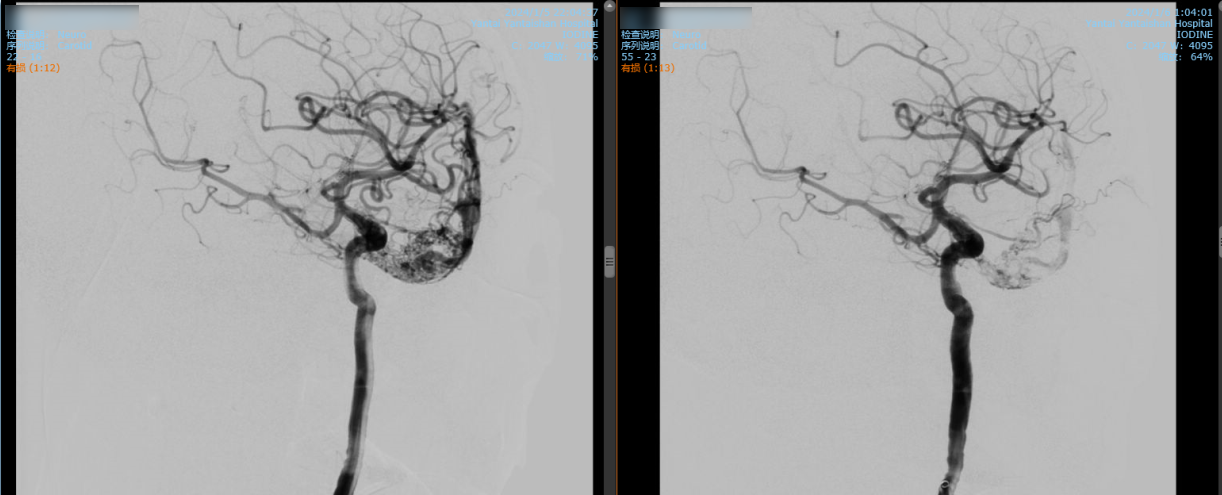

术前(图左),患者有颅内出血;术后(图右),患者的颅内出血消失。

术前造影检查(图左)显示,患者左侧大脑中动脉区域存在畸形血管团,累及脑干;术后(图右),畸形血管团消失。